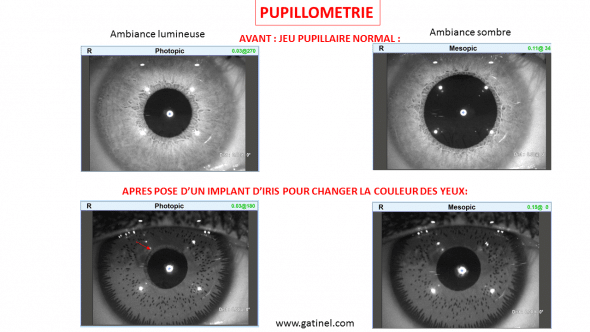

La comparaison entre une examen de pupillométrie effectué avant et après la pose d’implants d’iris montre la fixité du diamètre de la pupille artificielle de la prothèse d’iris:

Pupillométrie effectuée avant et après implant d’iris (les images sont en noir et blanc). L’implant d’iris possède un orifice central dont le diamètre est de 4 mm. Avant l’intervention, la pupille naturelle se dilate dans la pénombre (conditions d’examen mésopiques). Après la pose d’iris artificiel en avant de l’iris naturel, le jeu pupillaire n’est plus visible. En bas à gauche, on devine une frange d’iris naturel, le centrage de la pupille artificiel étant légèrement décalé vis à vis de la pupille naturelle (flèche)